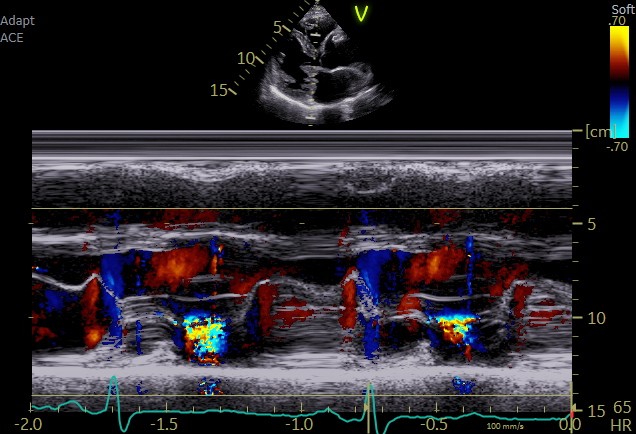

Color M modeにて逆流時相を確認すると逆流は収縮期後半に認める